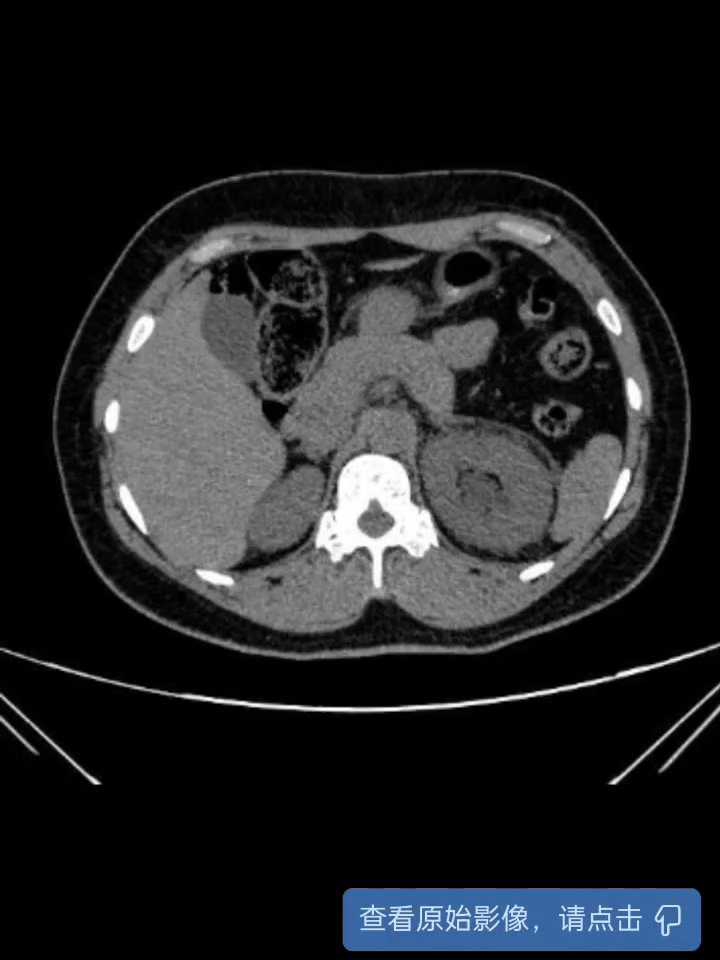

术前CT:

【临床诊断】:1.左侧输尿管结石并肾积水;2.左侧重复肾盂输尿管畸形。